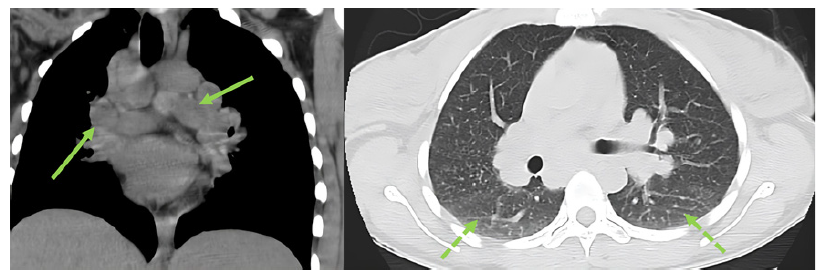

Abdominal ultrasound, contrasted tomography, and magnetic resonance cholangiopancreatography revealed mild hepatomegaly with a homogeneous liver and no other significant findings. Comprehensive study results were negative for infections, auto-immunity, heavy metal poisoning, metabolic diseases, and plasma cell dyscrasia (shown in Table 1). Despite the absence of respiratory symptoms, angiotensin-converting enzyme was elevated (200.7 U/L - normal range: 20-70 U/L). In this context, a chest radiological study was performed, revealing mediastinal and peribronchial adenopathies and a diffuse interstitial densification pattern in lung bases on computed tomography (shown in Fig. 1). Additionally, bronchoscopy identified whitish micronodules on the left lateral wall of the trachea and left main bronchus, with biopsies confirming non-caseating epithelioid granulomas. Immunophenotyping of bronchoalveolar lavage showed a CD4+/CD8+ lymphocyte ratio greater than 3.5. A liver biopsy was then performed (shown in Fig. 2), revealing multiple epithelioid granulomas located periportally and in the lobular areas, without necrosis. The histochemical study showed no evidence of microorganisms, including acid-fast bacilli (Ziehl-Nielsen) or fungal structures (PAS and Grocott); there was an absence of hyaline globule deposits, hemosiderin (Perls), and copper (rhodanine). In the immunohisto-chemical study, rare bile ducts were observed, and periportal he-patocytes exhibited an intermediate cell phenotype, suggesting chronic cholestasis. These findings were suggestive of HS.

Fig. 1. Thoracic computed tomography revealing multiple mediastinal and peribronchial adenopathies and diffuse interstitial densification pattern at the lung bases (see arrows).